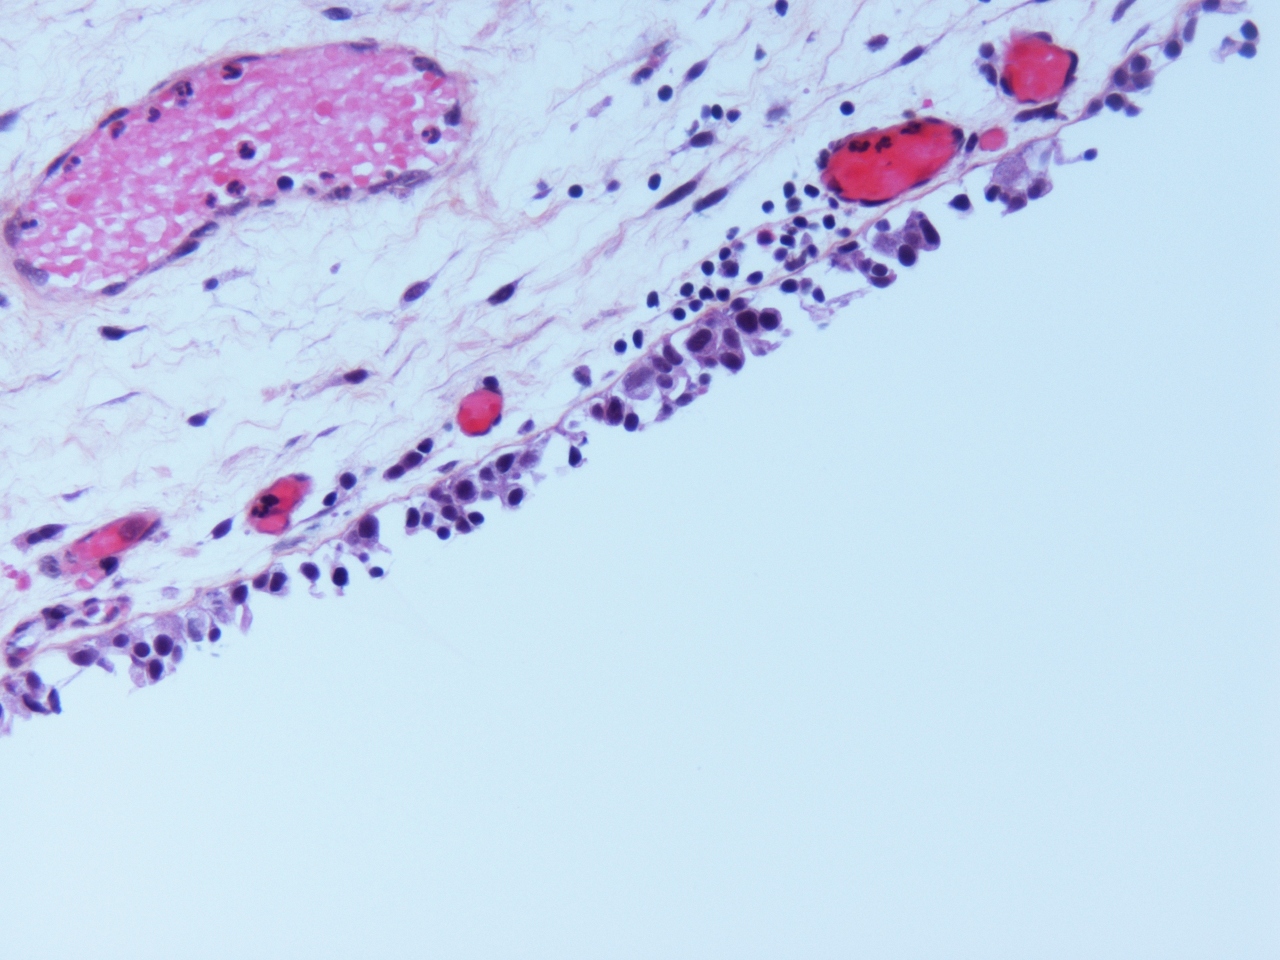

Bladder Flat Lesions

Case ID: 305